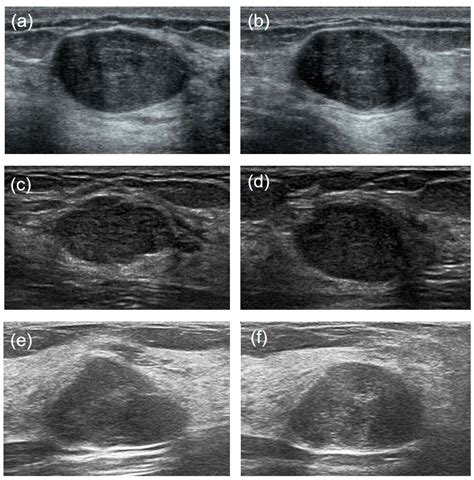

To differentiate a Phyllodes tumor breast from other breast conditions, clinicians employ a multi-modal diagnostic approach. Since imaging alone cannot definitively distinguish a phyllodes tumor from a fibroadenoma, a biopsy is typically required.

2. Imaging (Mammography/Ultrasound): Provides detailed views of the tumor's size, shape, and borders.

3. Core Needle Biopsy: A sample of the tumor tissue is removed using a hollow needle for microscopic analysis. This is the gold standard for diagnosis, although it can sometimes be difficult to distinguish between types on a small sample.